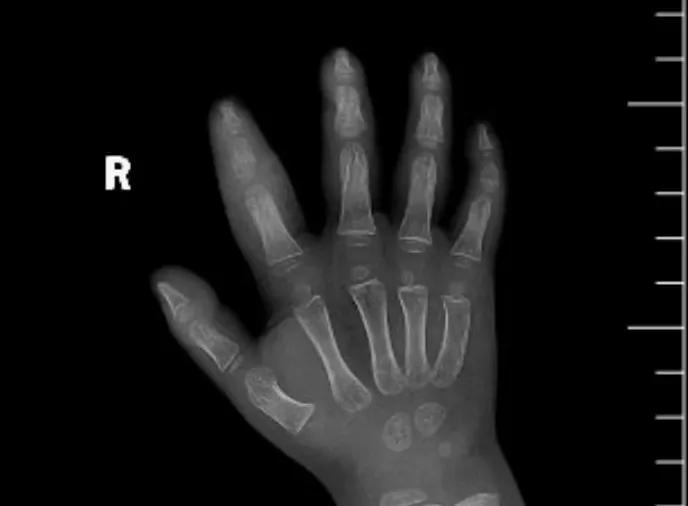

近日,市二院顯微外科接診一名3歲半的小患者,被玉米葉割傷右食指,因家長疏忽大意,導致一個小小的傷口竟然發展成了骨髓炎。來院時患兒右食指腫脹明顯,既不能伸也不能彎,皮膚發燙,疼得哇哇大哭。

第三天開始,月月哭鬧不止,一直說手疼,怎么哄也不行,于是在當地醫院治療了10來天,然而月月的手指依然腫得像個胡蘿卜,疼痛感依然存在。此時,月月的媽媽才覺得事情不大對勁,于是經過打聽,慕名來到市二院顯微外科。入院后,經檢查發現,月月的右食指骨質有侵蝕,骨骺有缺損,甚至會影響以后手指的發育。聽到這個消息,月月媽媽感覺心都揪住了。

隨后,經顯微外科團隊充分的討論,制定了科學細致的治療方案,為月月做了感染灶清除及手指的開放引流,并留取了標本做細菌培養,為進一步的合理用藥提供依據。經過兩周的治療,月月的手指終于順利消腫愈合,并且手指功能活動良好。說起這一個多月的煎熬,月月媽媽不禁落淚,但總算是治愈了,笑容又重新回到她們一家的臉上。